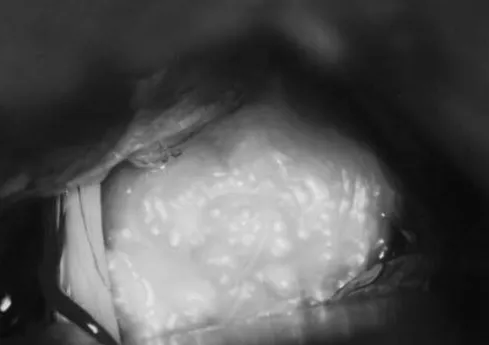

手术显微镜下观察CPA内"珍珠样"肿瘤位于前庭蜗神经上方,覆盖三叉神经。

内镜辅助下双手操作(内镜由自固定装置固定)。

根据Obrador和Lopez-Zafra的报道,由于表皮样囊肿具有不规则结节状表面和珍珠样光泽,Cruveilhier将其称为"珍珠样肿瘤"。表皮样囊肿由薄层包膜组成,内含柔软的白色物质,这是上皮衬里渐进性脱屑和角蛋白分解的结果。这种物质富含胆固醇,具有蜡样质地,形成同心层状结构。由于囊肿内容物的质地和无血管特性,其清除相对容易。然而,包膜可能与神经血管结构紧密粘连,使得完全切除的尝试具有风险。

手术中通过使用30°或70°视角的内镜,可以安全地观察和切除隐藏在精细神经血管结构后方的肿瘤部分。内镜在观察和切除延伸至Meckel腔的表皮样囊肿方面特别有用。通过乳突后枕下入路,可以在不扩大骨窗的情况下切除这些肿瘤部分。

INC施罗德教授提到在内镜视野下切除肿瘤部分而未使用显微镜;这被称为内镜控制显微外科。在此过程中,外科医生在观看监视器屏幕的同时操作常规显微外科器械。这种技术需要一定的训练,因为手眼协调在初期相当困难。然而,内镜是固定的,外科医生双手自由,可以像习惯的那样进行双手操作。为避免内镜插入后镜头起雾,我们在使用前将内镜置于37°C的无菌温盐水中。通过冲洗或擦拭清洁镜头。定期冲洗手术区域至关重要,因为内镜尖端可能变得非常热。当内镜位于颅神经前方时,必须进行冲洗以避免引起神经功能缺损。